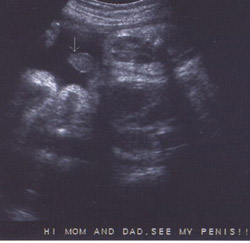

الولد

الأسبوع ال18